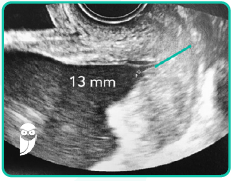

Gestante de 20 semanas, primigesta, sem comorbidades, veio realizar ultrassom morfológico do segundo trimestre com avaliação do colo uterino via vaginal e foi observada a imagem da figura abaixo.

Diante disso, qual é a conduta a ser realizada?